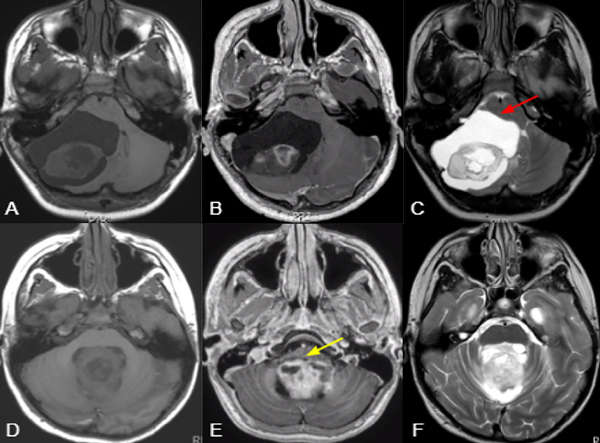

Los tumores centrales se definieron como aquellos emergiendo del vermis/paravermis o localizados en el IV ventrículo. Los tumores originados en un hemisferio cerebeloso con crecimiento medial y compresión del IV ventrículo no entran en esta categoría. (Figura 1)

Los tumores sólidos se categorizaron como lesiones cuyo componente sólido corresponde a más del 90% de su naturaleza. Se englobaron las lesiones quísticas independientemente de su presencia o ausencia de nódulo mural o componente sólido. (Figura 1,2)

Figura 1. Imágenes ilustrativas de RM ponderadas en T1 (A,D), T1+ gadolino (B,E) y T2 (C,F), comparando una lesión predominantemente hemisférica y quística con efecto de masa y desplazamiento troncal (flecha roja) (A;C), con otra central y sólida con invasión troncal (flecha amarilla) (D:F). En el primer caso es más factible lograr la RT y menor riesgo de requerimiento de manejo post operatorio de hidrocefalia o recurrencia, mientras que en el segundo presenta un mayor riesgo de RST, mutismo y necesidad de manejo postoperatorio de hidrocefalia o recurrencia.